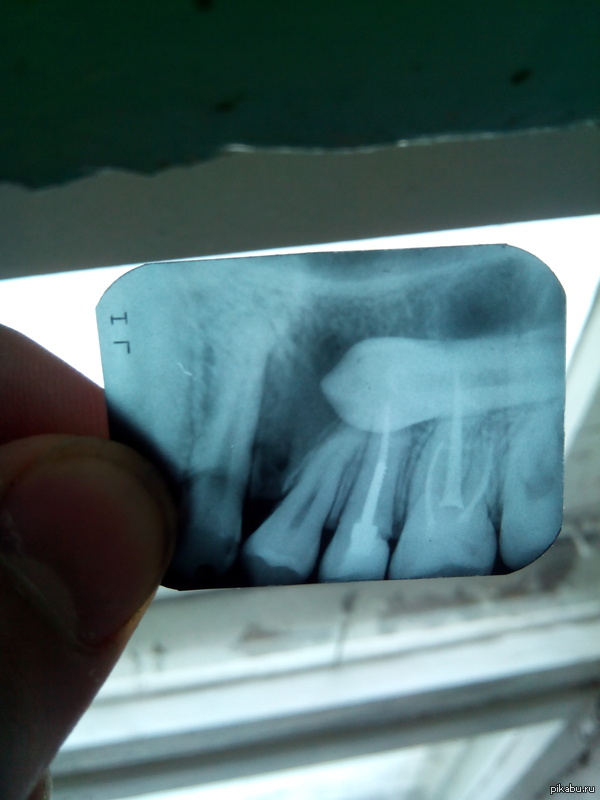

Для моих трёх подписчиков-дантистов.

В продолжение . Людей, которые "не в теме" прошу не обращать внимания и проходить мимо:)

-Ну тогда 100% удалять. Тут без вопросов. Так получилось что ваш зуб образовался в "гайморовой пазухе".

Решено удалять зуб. Когда ещё не определился.Также не определился где это делать, у нас в поликлинике это невозможно:Город небольшой, Железногорск, Кр.Край. Для его удаления требуется предварительное удаление нервов (Депульпирование зуба) у 4 и 8 зубов. (Слева и справа от 2-х уже запломбированных)